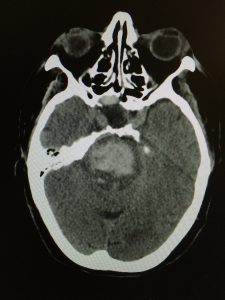

Patologia cerebrovascolare acuta

- emorragie subaracnoidee da rottura di aneurismi cerebrali (aSAH) o malformazioni artero- venose (MAV);

- emorragie intraparenchimali spontanee (ICH);